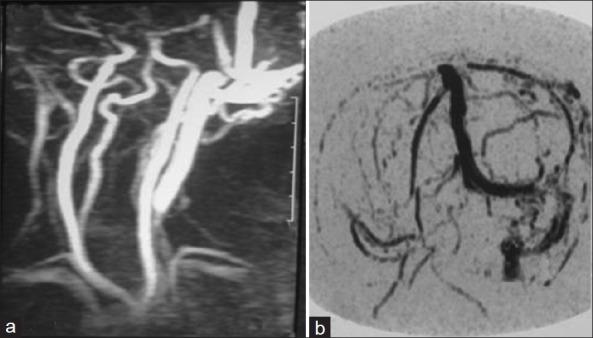

This is a retrospective case series study on nine patients with cirsoid aneurysms who were treated with surgical excision. Preoperative Planning for location, size, feeding arteries, and venous drainage of the lesions were done by plain and contrast enhanced CT, MRI, MR angiogram, and selective internal and external carotid angiograms. Complete surgical excision for the lesions was done. Postoperative evaluation of excision was done by cranial magnetic resonance angiography in all the patients. The mean follow up period was 34.1 (±7.62 STD) months.

The lesion was located in the occipital region in three (33.3%) cases, frontal region in two (22.2%) cases, temproparietal region in two (22.2%) cases, parietal region in one case (11.1%), and vertex in one case (11.1%). The superficial temporal artery was involved in seven (77.8%) cases, the occipital artery was involved in six (66.7%) cases, the posterior auricular artery was involved in five (55.6%) cases, the supraorbital artery was involved in two (22.2%) cases and the middle meningeal artery was involved in two (22.2%) cases. Total excision of the lesion was achieved in eight patients and en bloc resection and primary closure was done in one patient. Postoperative magnetic resonance angiogram showed no residual lesion in all patients. No postoperative complication related to the surgery had occurred. No recurrence had occurred during the follow-up period (mean 34.1 ± 7.62 STD months).

这是一项对9例接受手术切除治疗的头皮蔓状动脉瘤患者的回顾性病例系列研究。通过平扫及增强CT、MRI、磁共振血管造影以及选择性颈内、外动脉血管造影对病变的位置、大小、供血动脉和静脉引流进行术前规划。对病变进行完整的手术切除。所有患者术后均通过头颅磁共振血管造影对切除情况进行评估。平均随访期为34.1(±7.62标准差)个月。

病变位于枕部3例(33.3%),额部2例(22.2%),颞顶部2例(22.2%),顶叶1例(11.1%),头顶1例(11.1%)。颞浅动脉受累7例(77.8%),枕动脉受累6例(66.7%),耳后动脉受累5例(55.6%),眶上动脉受累2例(22.2%),脑膜中动脉受累2例(22.2%)。8例患者实现了病变的完全切除,1例患者进行了整块切除并一期缝合。术后磁共振血管造影显示所有患者均无残留病变。未发生与手术相关的术后并发症。随访期间(平均34.1±7.62标准差个月)未发生复发。